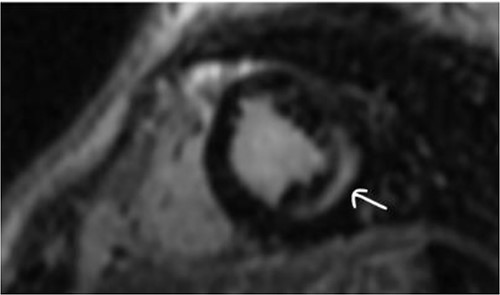

Clinically, both patients complained of worsening palpitations over the last few months with no associated dyspnea or tiredness. A Holter examination recorded 14 444 VES and 212 NSVT, with very similar results in both sisters. The echocardiography revealed a myxomatous Barlow mitral valve with anterior and posterior leaflet prolapse and two regurgitant jets resulting in moderate to severe mitral valve regurgitation as well as mitral annular disjunction in both cases (Figs 1 and 2). A cardiac MRI on a 3 T Lumina Siemens revealed at the mid-left ventricular level, a midwall fibrosis in the midlateral myocardium (Figs 3 and 4) and confirmed a mitral annular disjunction of 12 mm (Figs 5 and 6). Additional findings included a dilated LV with mildly depressed contractility, no visible myocardial scarring, no structural heart disease and a normal sized RV with mildly depressed contractility.

In our reported case, both patients underwent an S-ICD implantation before discharge as they were both considered to have a high risk of sudden cardiac death. The role of ICD implantation as primary prevention in such cases is unclear as available data are limited. We consider an individual risk stratification of such patients appropriate taking into consideration the arrhythmogenic potential of MAD, myocardial fibrosis, medical history of malignant arrhythmias and family history. In our case, both sisters presented with a large longitudinal distance of MAD in magnetic resonance, severe Barlow’s disease at a young age, and a reported case of sudden cardiac death in the family all of which are predictors of arrhythmias in MAD [6]. The choice of subcutaneous ICD implantation vs. transvenous was made solely on the patient’s age and preservation of their quality of life.